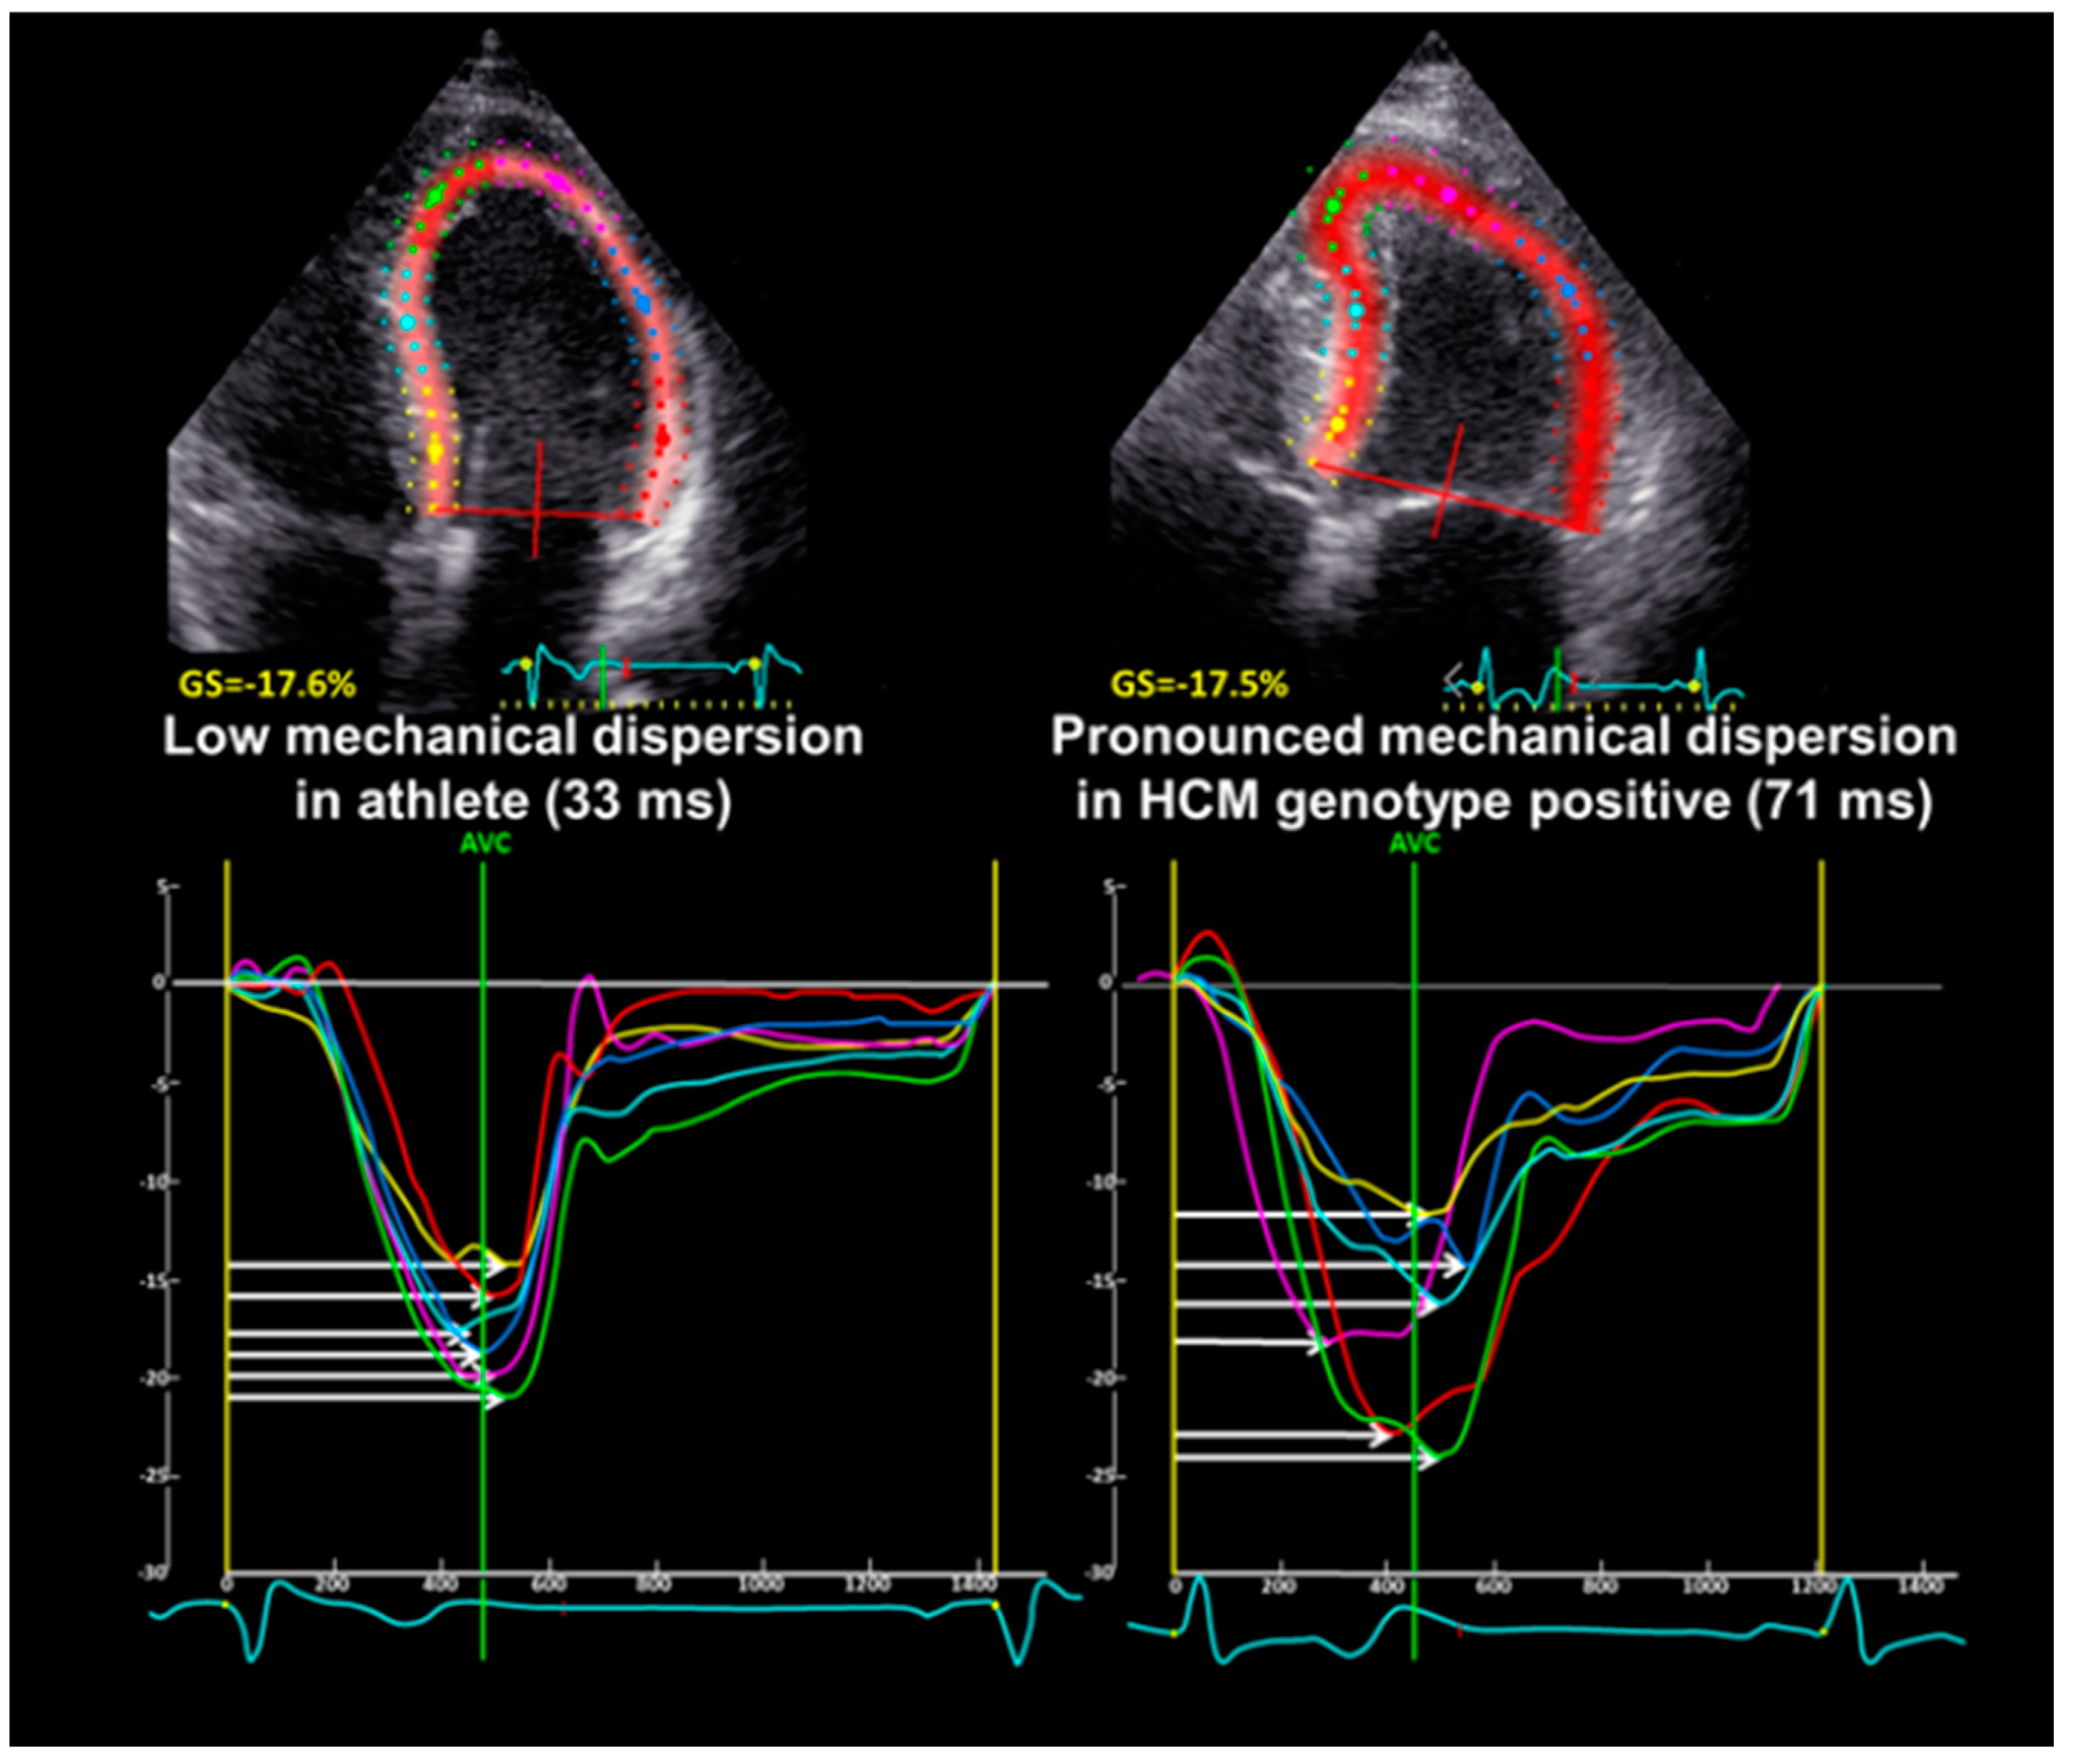

| LV mechanical dispersion, ms | 40 ± 11 | 54 ± 16 | 0.001 |

| Mechanical dispersion, ms | 40 ± 11 | 54 ± 16 | 0.001 | >44 | 0.78 | 0.65–0.91 |

| Global longitudinal strain, % | −18.9 ± 1.8 | −18.1 ± 3.7 | 0.28 | >−17.7 | 0.58 | 0.40–0.76 |

- Schnell, F.; Matelot, D.; Daudin, M.; Kervio, G.; Mabo, P.; Carré, F.; Donal, E. Mechanical Dispersion by Strain Echocardiography: A Novel Tool to Diagnose Hypertrophic Cardiomyopathy in Athletes. J. Am. Soc. Echocardiogr. 2017, 30, 251–261. [Google Scholar] [CrossRef]